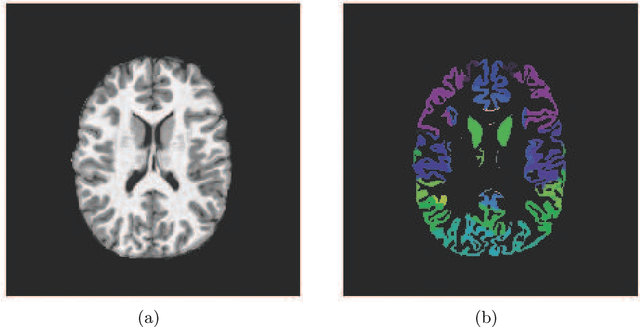

The ABCD Neurocognitive Prediction Challenge is a community driven competition asking competitors to develop algorithms to predict fluid intelligence score from T1-w MRIs. In this work, we propose a deep learning combined with gradient boosting machine framework to solve this task. We train a convolutional neural network to compress the high dimensional MRI data and learn meaningful image features by predicting the 123 continuous-valued derived data provided with each MRI. These extracted features are then used to train a gradient boosting machine that predicts the residualized fluid intelligence score. Our approach achieved mean square error (MSE) scores of 18.4374, 68.7868, and 96.1806 for the training, validation, and test set respectively.